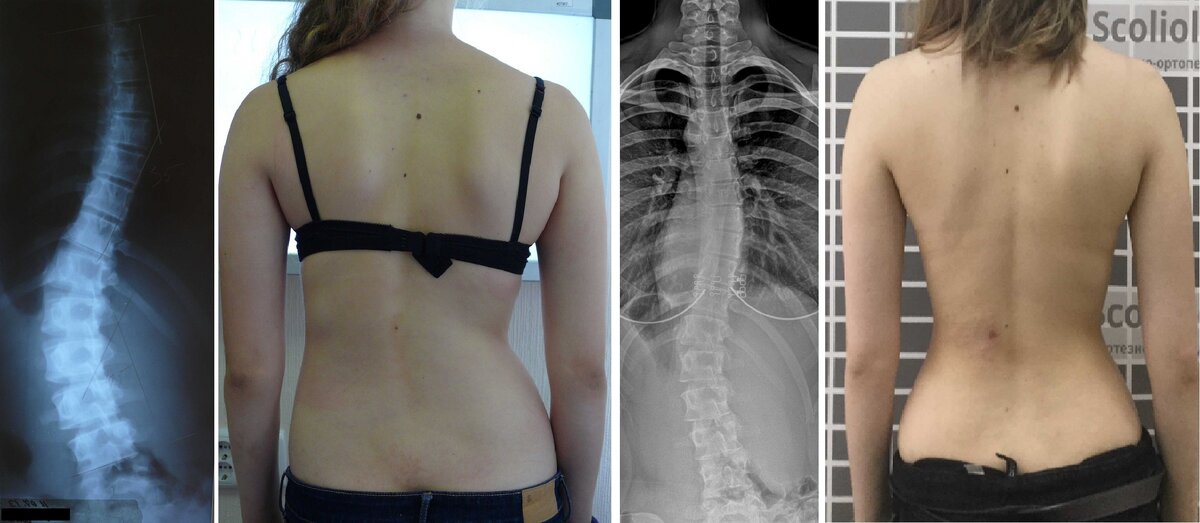

Результаты корсетотерапии

15-34-48 градусов.

Сейчас в 18 лет 8-20-18 градусов. Точки роста закрыты, корсет больше носить не надо. Прекрасный косметический эффект.